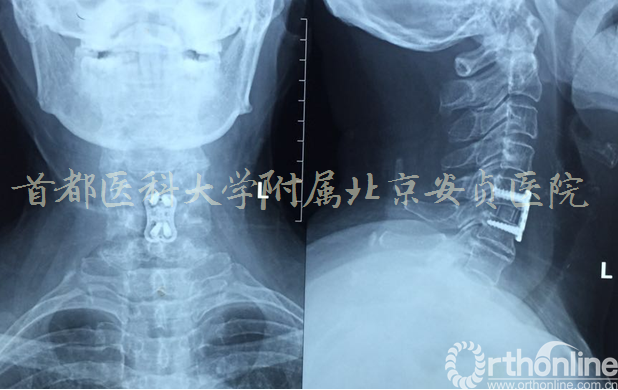

C5/6 ACDF 术后2天

术后情况:

颈后部、双上臂、腰部、骶尾部疼痛明显减轻

胸背部束带感消失

行走后胸憋较前明显好转

可以挺直腰背行走

JOA评分17分

颈部、双上臂疼痛VAS评分1分。

目前在随访中,患者对手术效果非常满意。已经能独立行走及完成日常家务劳动。

术后一个月